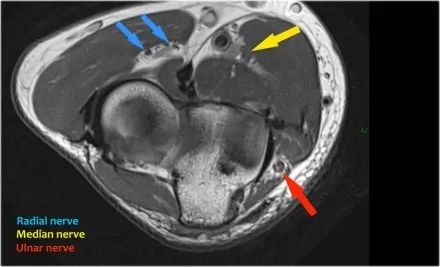

桡神经:在桡骨头水平可以最好地识别桡神经,在那里你可以看到桡骨隧道中的浅表和深支(箭头)。这是寻找桡神经的非常一致的地方。